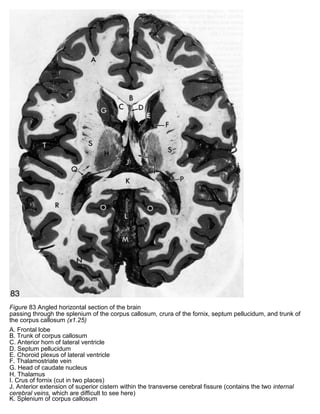

Figure 83 Angled horizontal section of the brain

passing through the splenium of the corpus callosum, crura of the fornix, septum pellucidum, and trunk of

the corpus callosum (x1.25)

A. Frontal lobe

B. Trunk of corpus callosum

C. Anterior horn of lateral ventricle

D. Septum pellucidum

E. Choroid plexus of lateral ventricle

F. Thalamostriate vein

G. Head of caudate nucleus

H. Thalamus

I. Crus of fornix (cut in two places)

J. Anterior extension of superior cistern within the transverse cerebral fissure (contains the two internal

cerebral veins, which are difficult to see here)

K. Splenium of corpus callosum

L. Great cerebral vein (within superior cistern)

M. Superior surface of cerebellum N. Occipital lobe

O. Calcarine sulcus

P. Choroid plexus within inferior horn of lateral ventricle (frequently seen in CT scans at this location)

Q. Tail of caudate nucleus R. Temporal lobe

S. Corona radiata (just above internal capsule)

T. Lateral sulcus (with several branches of middle cerebral artery within it)

Figure 83 Angledhorizontal section of the brain passing through the splenium of the corpus callosum, crura of the fornix, septum pellucidum, and trunk of the corpus callosum (x1.25) A. Frontal lobe B. Trunk of corpus callosum C. Anterior horn of lateral ventricle D. Septum pellucidum E. Choroid plexus of lateral ventricle F. Thalamostriate vein G. Head of caudate nucleus H. Thalamus I. Crus of fornix (cut in two places) J. Anterior extension of superior cistern within the transverse cerebral fissure (contains the two internal cerebral veins, which are difficult to see here) K. Splenium of corpus callosum

L. Great cerebralvein (within superior cistern) M. Superior surface of cerebellum N. Occipital lobe O. Calcarine sulcus P. Choroid plexus within inferior horn of lateral ventricle (frequently seen in CT scans at this location) Q. Tail of caudate nucleus R. Temporal lobe S. Corona radiata (just above internal capsule) T. Lateral sulcus (with several branches of middle cerebral artery within it)